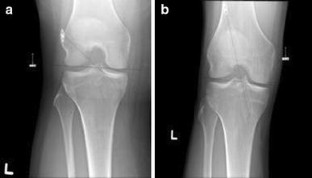

This is a single-blinded, prospective, randomized controlled trial. Participants were randomized to undergo ACL reconstruction using the AMP or TT approach. The primary outcome measure was the ACL quality of life (ACL-QOL), and secondary outcomes were the IKDC knee assessment, side-to-side difference in anterior–posterior knee laxity (KT-1000) and tunnel orientation (X-ray findings) at preoperative, 3, 6, 12, and 24 months postoperative. Statistical comparisons were performed using a series of t tests for independent groups with equal variance.

Ninety-six participants were consented and randomized between 2007 and 2011 with eight excluded postrandomization. Mean (SD) preoperative ACL-QOL was 33 (13) for TT and 36 (17) for AMP and improved significantly (p < 0.001) in both groups to 79 (18) and 78 (18) at 24 months postoperative, respectively. The preoperative median IKDC grade for both groups was C and improved similarly in both groups at 24 months (n.s.). There was no side-to-side difference in knee laxity based on KT-1000 measurements with a mean (SD) 1 (3) mm between affected and unaffected limbs in the TT group compared to 1 (3) mm for the AMP group. A significant difference was found in femoral tunnel orientation with the AMP group at 43° (7) and the TT group 58° (8) in the coronal plane (p < 0.001).

Fig. 1

Fig. 2